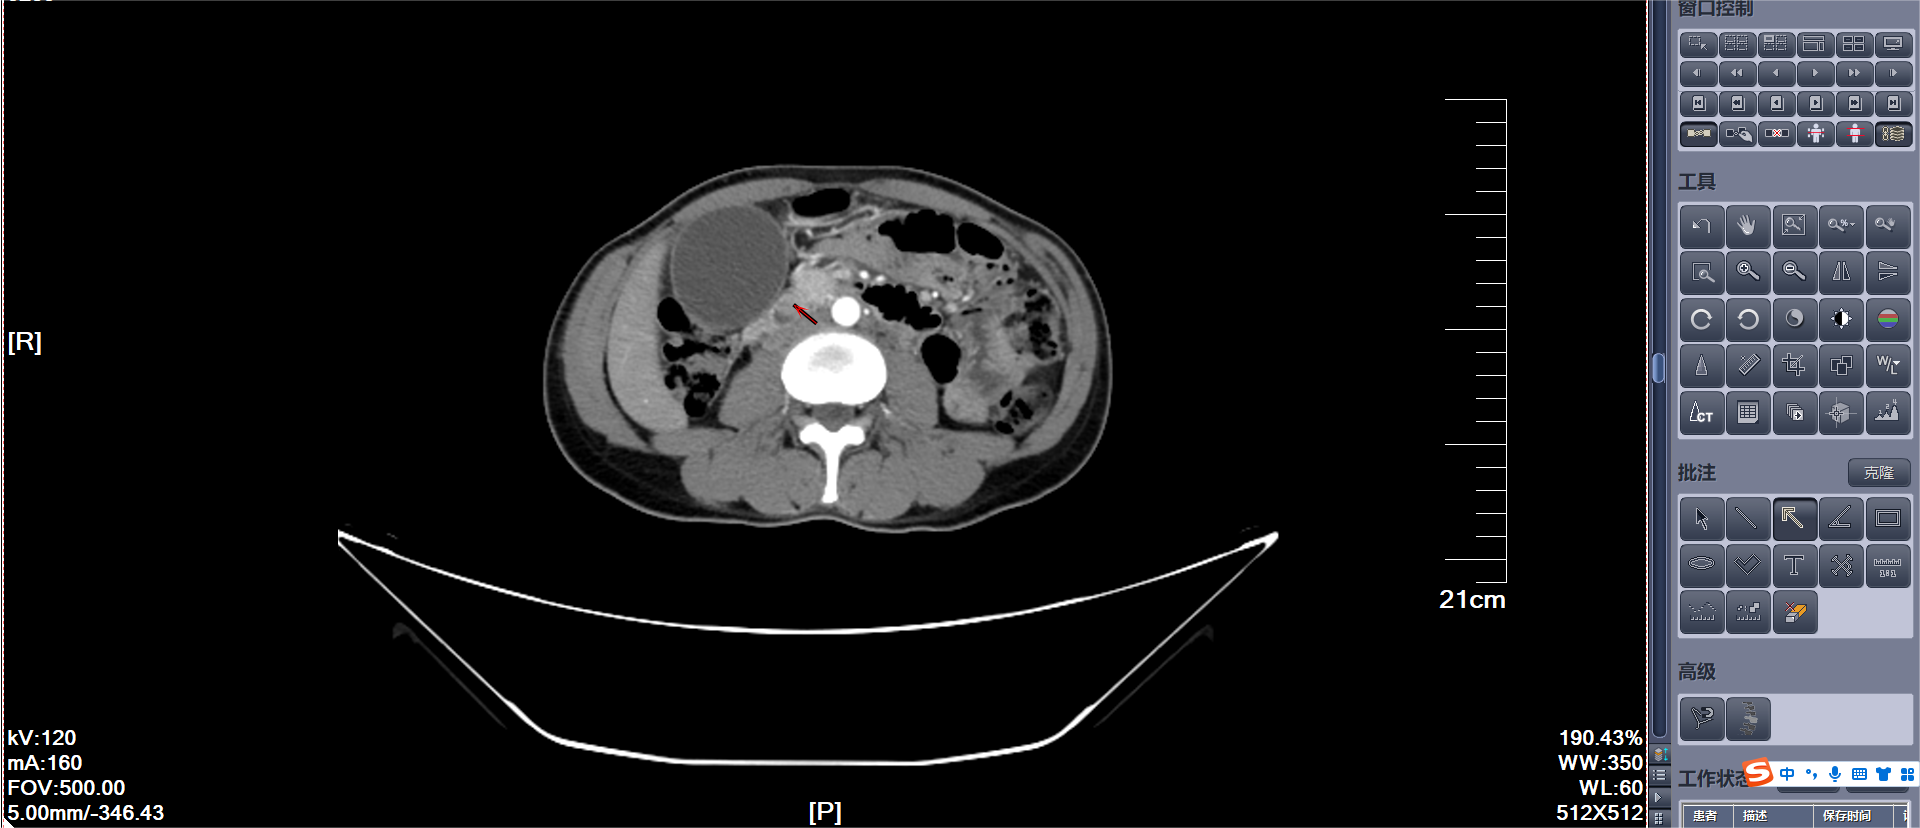

▶ 腹部增强CT、增强磁共振+MRCP均提示十二指肠壶腹部结节灶占位,考虑壶腹部周围癌,伴肝内外胆管、胰管、胆囊扩张。

A:十二指肠壶腹部结节状占位(红色箭头);

B:扩张的胆囊、胆总管、胰管(红色箭头)增强CT提示十二指肠壶腹部结节状占位:考虑壶腹部癌可能并肝内外胆管、胰管扩张。